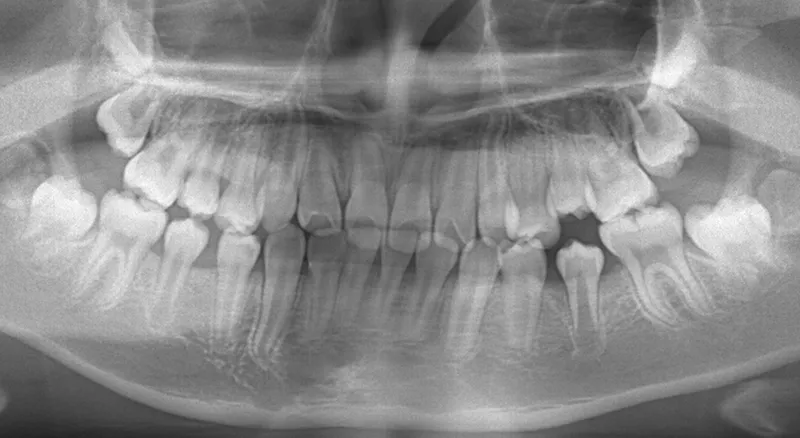

【子供の矯正(一期)】叢生・埋伏歯・受け口・永久歯が生える隙間がない・非抜歯症例・9歳女子【K.T様】

• 初診

初診時年齢 小学校2年生 (女性) 主訴 受け口・がたがた

診断名 埋伏歯・反対咬合・叢生 装置名

拡大床

抜歯の有無 非抜歯 治療期間・通院回数 2年 10ヶ月 / 29回

レントゲンを撮ってみると犬歯の萌出方向がずれていました。

先ずは萌出スペースを確保してから開窓術を行い、犬歯を正しい方向へ誘導しました。

初診